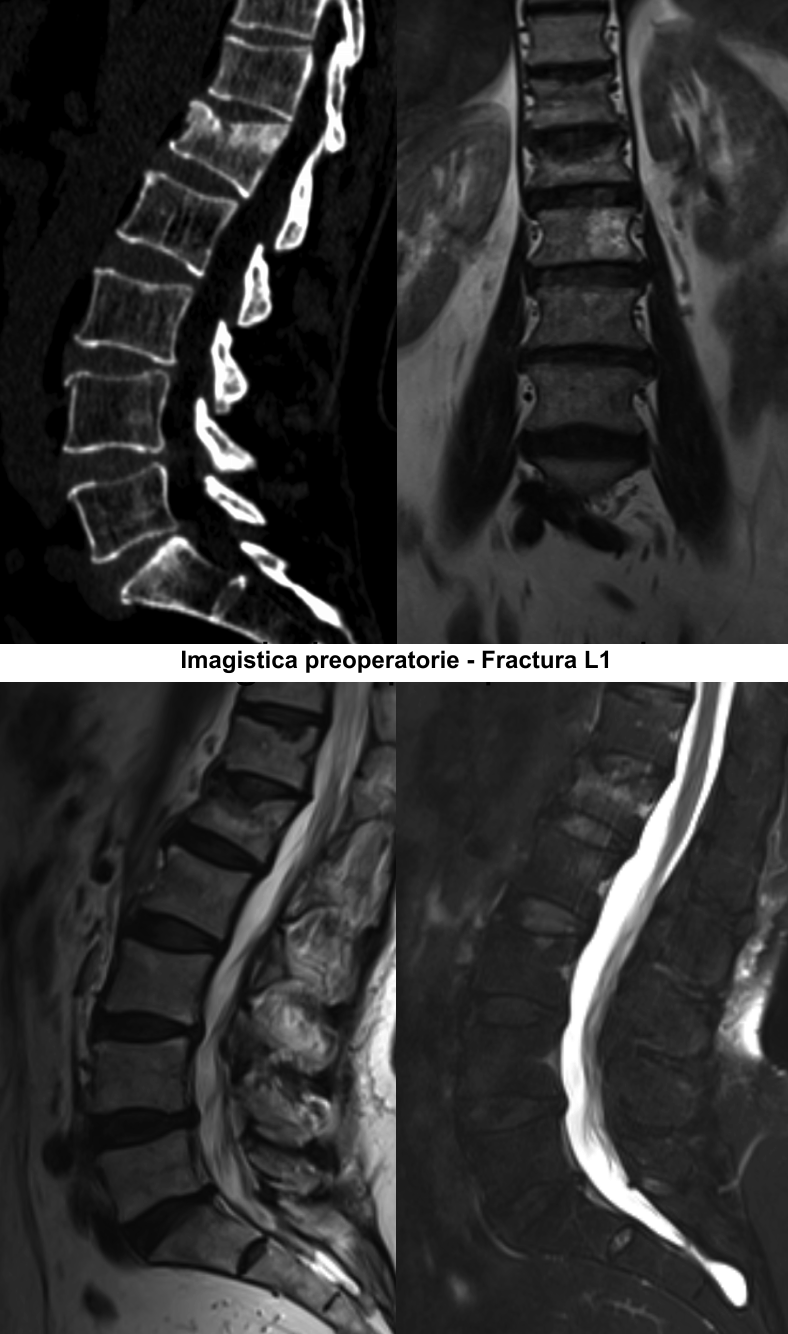

În urma investigaţiilor imagistice prin CT şi IRM a coloanei lombare, a fost stabilit diagnosticul Fractură tasată a corpului vertebral LI gr.II şi Hemangiom agresiv al hemicorpului vertebral LII pe stânga. Luând în considerare datele clinice şi paraclinice, s-a decis de a trata simultan aceste două vertebre, prin combinarea a două tehnici chirurgicale minim invazive – vertebroplastia percutanată şi kyfoplastia cu baloane expandabile.

Vertebroplastia percutanată (VTP) reprezintă injectarea unui ciment acrilic (metilmetacrilat) în vertebra patologic modificată sub control fluoroscopic sau tomografic. Această tehnică a fost propusă în 1984 de către neurochirurgul francez Pierre Galibert pentru tratamentul preoperator al unui hemangiom agresiv de vertebră cervicală, pentru a diminua hemoragia intraoperatorie. Ulterior, vertebroplastia a fost propusă pentru tratamentul fracturilor vertebrale osteoporotice şi în metastazele vertebrale cu sindrom algic pronunţat.

Kyfoplastia reprezintă o procedură minim invazivă în timpul căreia chirurgul introduce în corpul vertebral un tub cu un balon expandabil. Sub control fluoroscopic are loc expansionarea balonului în corpul vertebral, cu restabilirea înălţimii corpului vertebral şi corijarea diformităţii kifotice. Ulterior, în cavitatea formată de balon, se introduce cimentul acrilic, ceea ce contribuie la consolidarea vertebrei.

Majoritatea fracturilor vertebrale au loc în segmentul toracic inferior sau lombar superior şi sunt cauzate de traumatisme, osteoporoză sau tumori ale coloanei vertebrale. Scopul operaţiei este de a „întări” vertebra fracturată cu ciment special predestinat acestor scopuri. Vertebra în care a fost introdus cimentul devine mai rigidă, mai stabilă, iar în urma acestui fapt are loc diminuarea semnificativă a durerilor preoperatorii. Eficienţa tratamentului prin vertebroplastie şi kyfoplastie este de peste 90% în funcţie de tipul şi localizarea fracturii vertebrale. Acest tip de operaţii este unul sigur, poate fi aplicat pacienţilor în vîrstă, care suferă cel mai frecvent de osteoporoză, iar rata complicaţiilor se situează sub 1%.